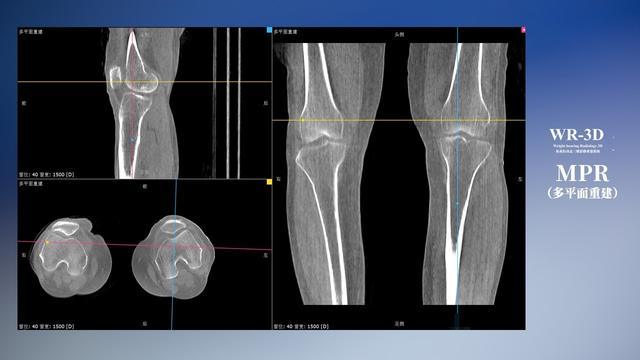

在負重位狀態下,數字化X線三維掃描與重建,能夠更好的呈現受檢者關節受力改變的狀態。安健科技創新的WR-3D動態三維影像重建系統,通過數字化X線攝影完成三維掃描并重建三維影像信息,包括斷層圖像重建、MPR多平面重建、MIP重建以及VR體繪制。其掃描時間短,劑量相較于CT設備大幅縮減,同時成本更低,在臨床診斷以及醫療方案制定中具有極大的價值意義。而相較于普通平片下的負重位掃描,負重位動態三維影像重建技術能夠避免二維狀態下的組織結構重疊、密度分辨率不足、組織解剖結構難以分辨等問題。WR-3D支持多角度的三維觀察,能全面的呈現被檢查部位在多個角度下的三維影像信息,極大的降低了二維負重位檢查帶來的漏診率。

安健科技WR-3D負重位動態三維影像重建圖像